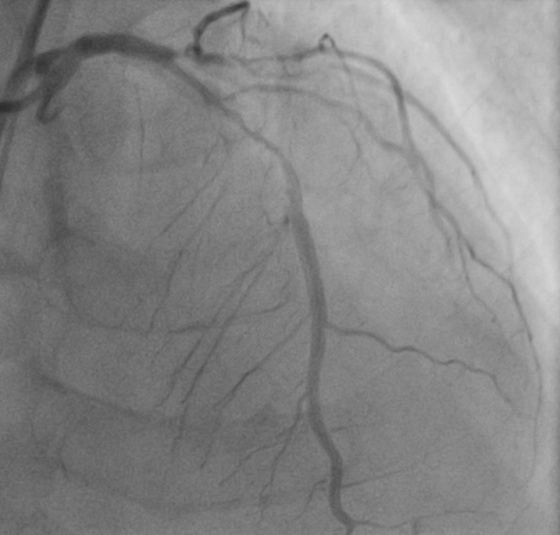

时间就是生命,每一分每一秒都关乎患者安危。抵达医院后,心血管内科在刘学波主任的指挥下迅速响应,医护人员第一时间投入到紧急救治工作中。王明的治疗难度极大,因多年患有糖尿病,心脏三根主要血管均存在重度弥散性钙化病变,外周血管状况也差,且肾功能不全、贫血。经过纠正心衰治疗病情相对稳定后,1月13日,在前期充分的药物治疗基础上,刘学波、来晏、姚义安、钱军等医生对患者行冠脉造影术,提示心脏三根冠脉均存在重度狭窄。其中最重要的左前降支为重度钙化病变,并且术中患者血压偏低,医护人员当机立断,为患者植入主动脉内球囊反搏(IABP),针对严重钙化的血管,来晏主任医师精准运用冠脉内冲击波碎石术(震波球囊)等专业技术破解治疗难题,成功在左前降支植入支架,有效疏通狭窄血管,手术全程顺利,为患者生命安全奠定坚实基础。

支架术前